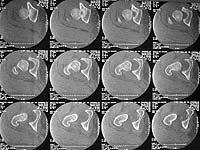

20 year old obese male presents after MVC. He was initially treated at an outside hospital but despite repeated closed reductions and traction the patient could not be held reduced. He was transferred to my hospital where we also attempted closed reduction. The patient reduced but was extremely unstable. Post-reduction xrays showed a nonconcentric reduction and CT scan showed bone fragments in the joint. The dislocation can be seen in the CT scan.

The upper CT images demonstrate a very peripheral and incomplete anatomical "dome" (see axial images 1,2,and 3)...some would call this acetabular dysplasia... but in this patient it's also in association with traumatic disruption of the all important local soft tissue envelope, hence clinical instability.

You'll see this "shallow" dome appearance frequently, if you look for it in patients with pelvic/acetabular CTs.